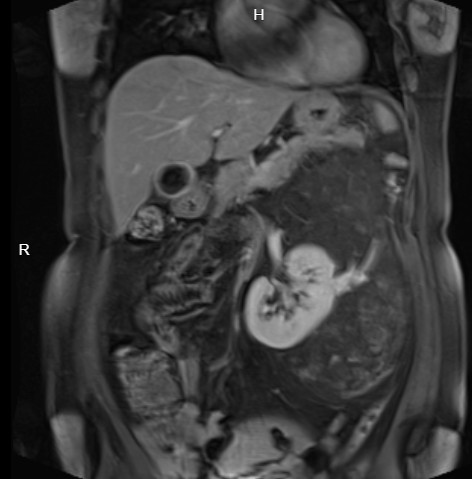

图片发自160App

腹膜后血管平滑肌脂肪瘤的基本概述

腹膜后血管平滑肌脂肪瘤是一种较为少见的良性肿瘤,它主要由平滑肌、血管及成熟型脂肪细胞这三种组织学成分构成。该肿瘤可发生在0~77岁的任何年龄,且无明显性别差异。

|磁共振|在发现肿瘤范围及其与周围组织和血管的关系时,优于CT||